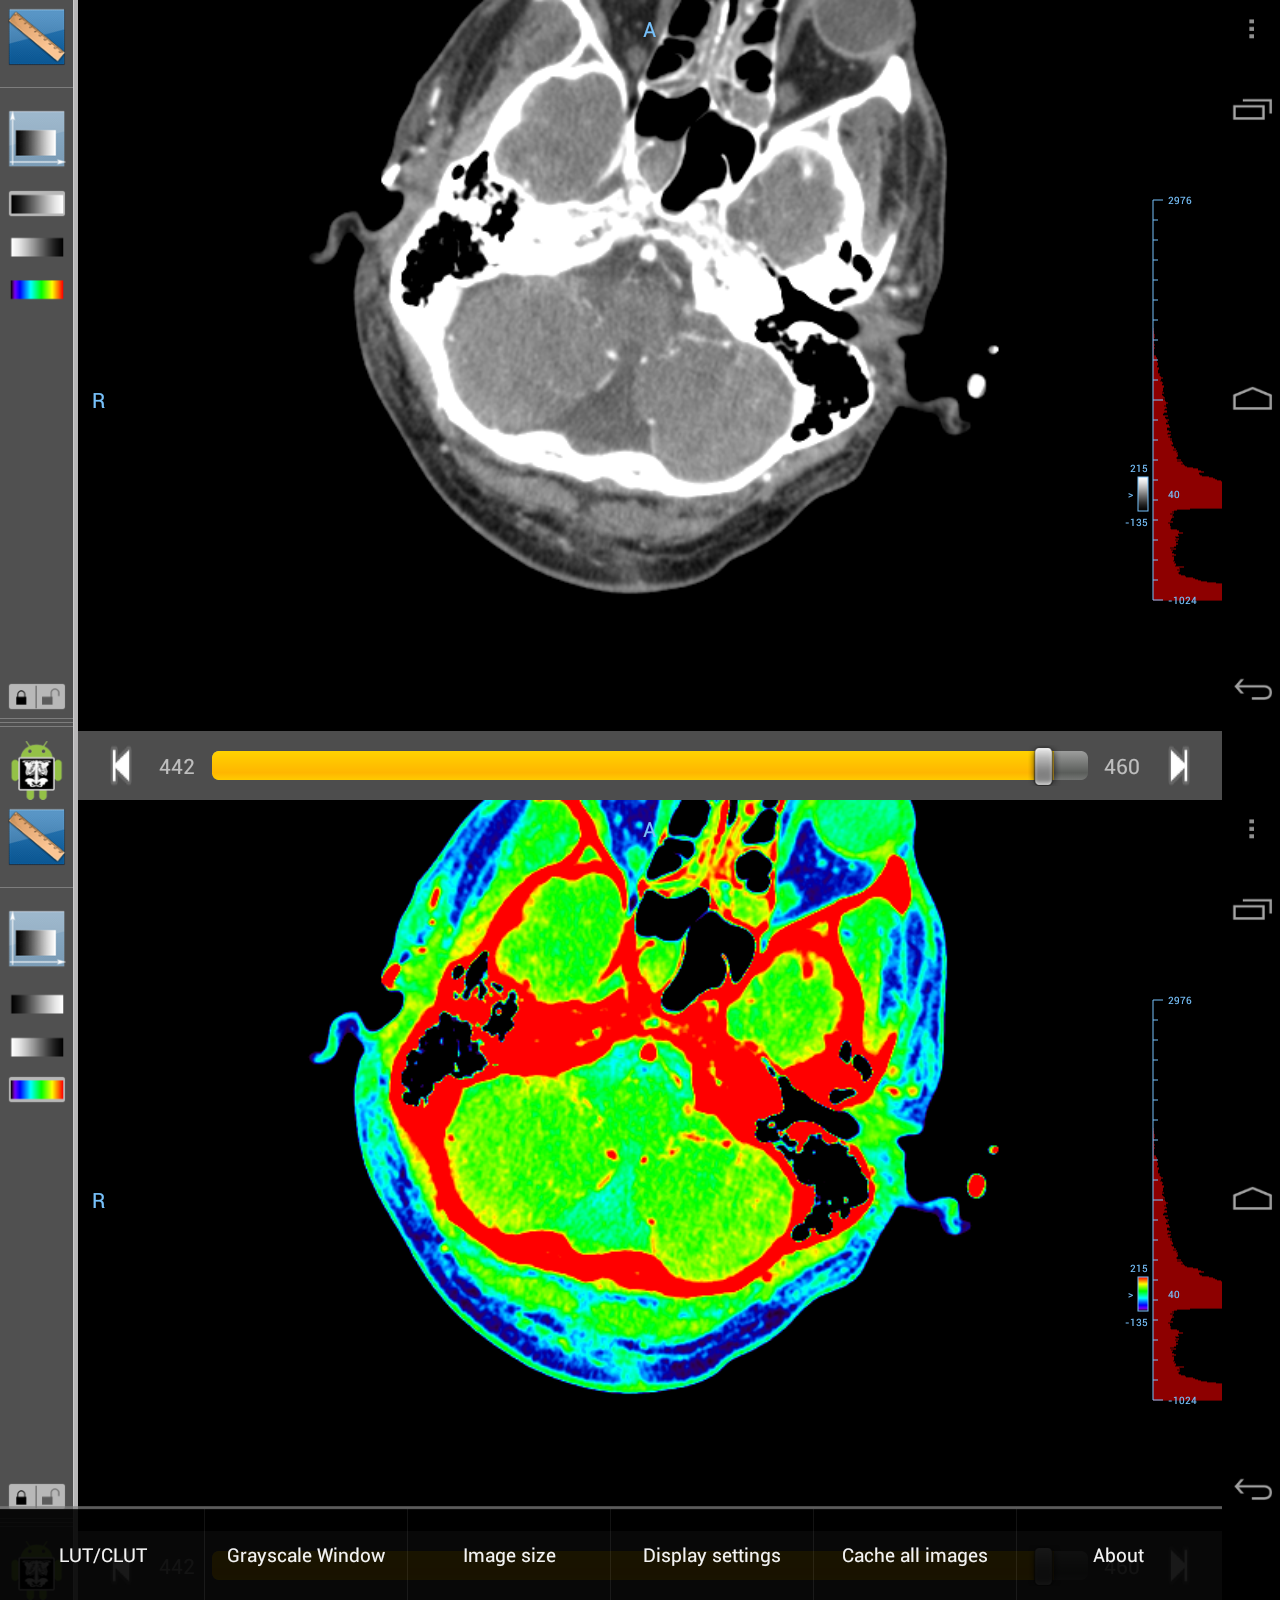

Droid DICOM Viewer — Röntgenbilder am Androiden betrachten